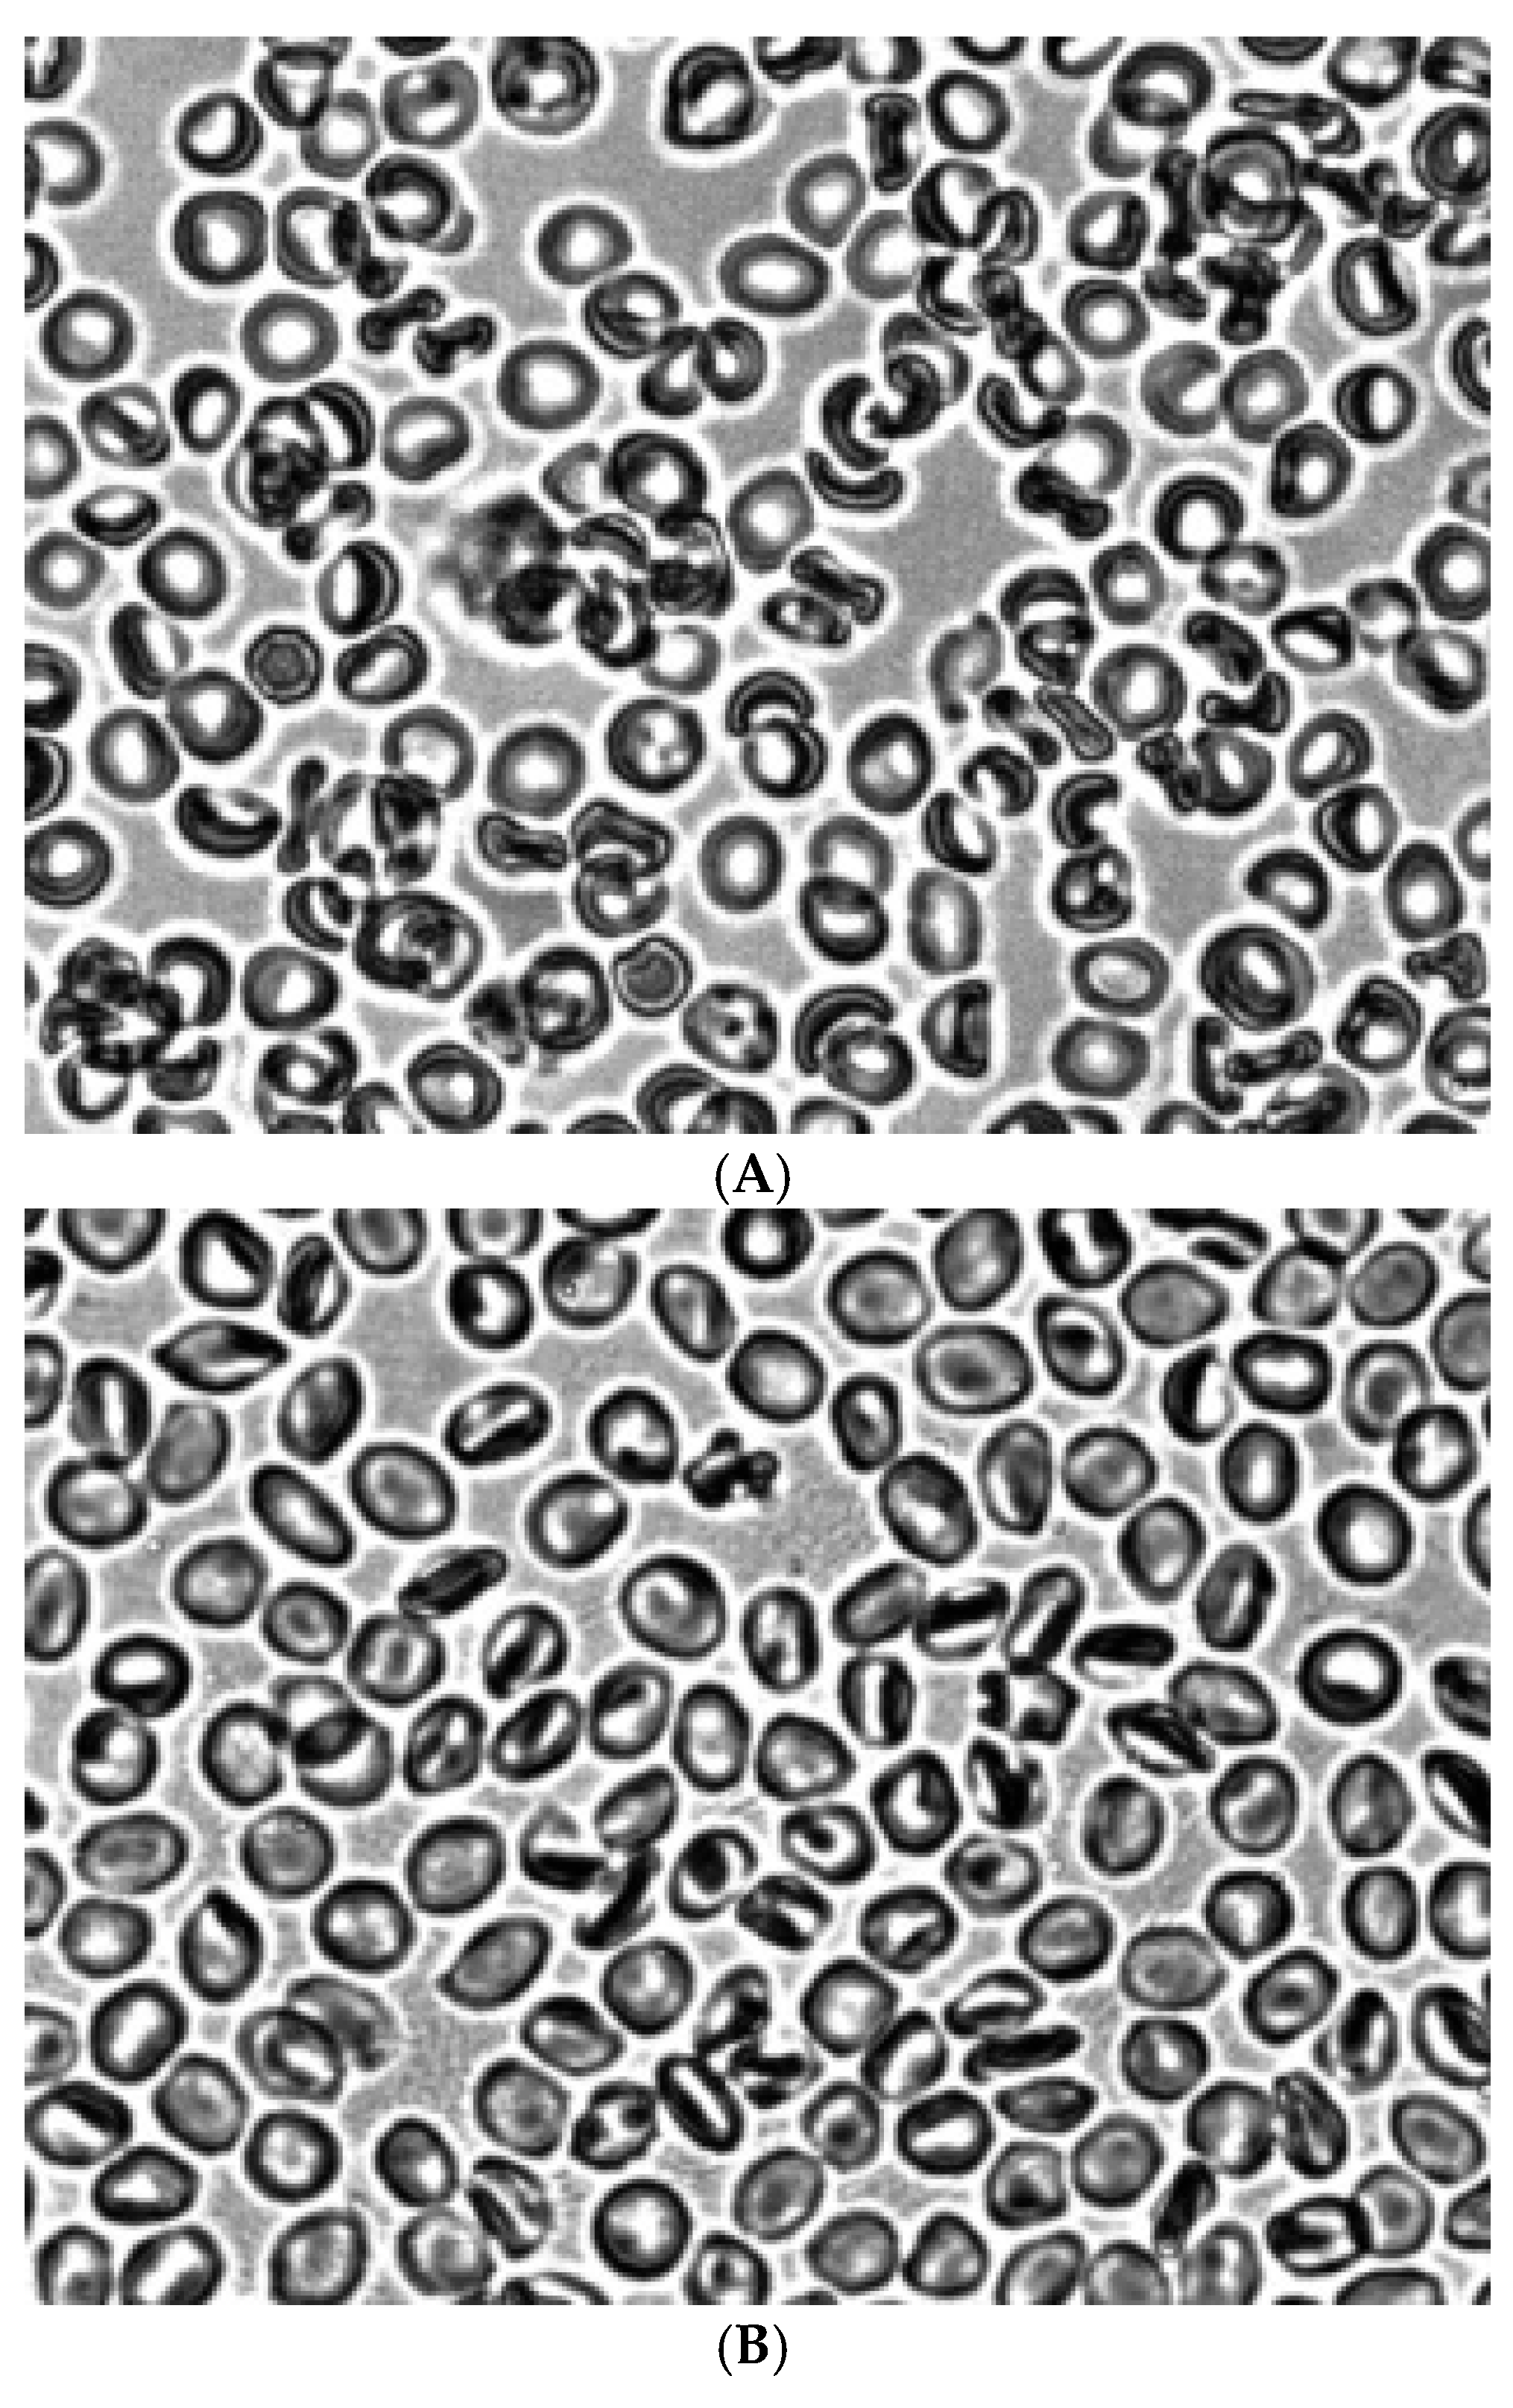

Figure 2 shows the morphology of RBCs before (Figure 2A) and during the creation of shear stress in the shear flow (Figure 2B). It can be seen that under shear stress, the bulk of the discocytes turn into stomatocytes. Stomatocytes fixed in a glutaraldehyde solution were aggregated after being placed in autologous plasma (Figure 4A) and a 3% dextran 70 solution (Figure 5A).

Figure 2. Morphology of RBCs before (A) and in the shear flow at a shear stress of 3 Pa (B). Fixation with glutaraldehyde. Magnification 1000x.